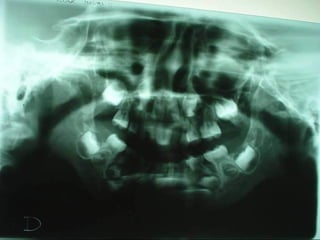

Cefalometría elementalCefalometría elemental

Se observa el número total de órganos dentarios incluyendo

terceros molares.

No hay tratamiento de conductos radiculares

Buen trabeculado óseo de tipo I

Se observa elnúmero total de órganos dentarios incluyendo terceros molares. No hay tratamiento de conductos radiculares Buen trabeculado óseo de tipo I Se observa el número total de órganos dentarios incluyendo terceros molares. No hay tratamiento de conductos radiculares Buen trabeculado óseo de tipo I